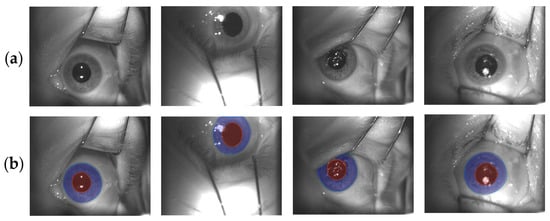

The proposed framework used the same U-Net structure for three different tasks, which operated in cascade with respect to each other. The first one aimed at roughly identifying the eye within the original image and at extracting an ROI around it. The U-Net training for this first task, namely the ROI U-Net, was performed using the original frames without any pre-processing operations and extracted directly from the ETS recordings (Figure 2a). The corresponding binary masks are depicted in Figure 2c and are composed by merging iris and pupil structures (Figure 2b). As will be explained in the U-Nets cascade section, the second and third tasks consisted respectively of iris and pupil detection within an ROI extracted from the original image. These networks are called Pupil U-Net and Iris U-Net, respectively. The ROI is a smaller portion of the image that should include both the structures and excludes background features. In order to maximize the iris and pupil prediction capabilities, the training process was performed by using the 350 × 350 pixels ROI manually extracted from the video frames. Accordingly, the same ROI was identified within the masks. This operation allowed the definition of the ground truth for the two training processes. Figure 2, in panel (d) and (e), depicts the ROI-masks used respectively for the iris and pupil training procedures. The dimensions of the binary masks were 350 × 350 pixels.

Figure 2.

(a) Original images used for U-Net training and testing. They were extracted directly from ETS recordings. The green squares identify the ROI areas that have been manually selected by the clinical operator. They were used during the U-Net training and testing for iris and pupil detection. (b) Manual contours of iris (grey) and pupil (white). (c) Ground truth images in which iris and pupil structures are merged together and used for training and testing the ROI U-Net. (d,e) iris and pupil binary ROIs extracted from the original masks. They were used for training and testing the iris and pupil U-Nets.